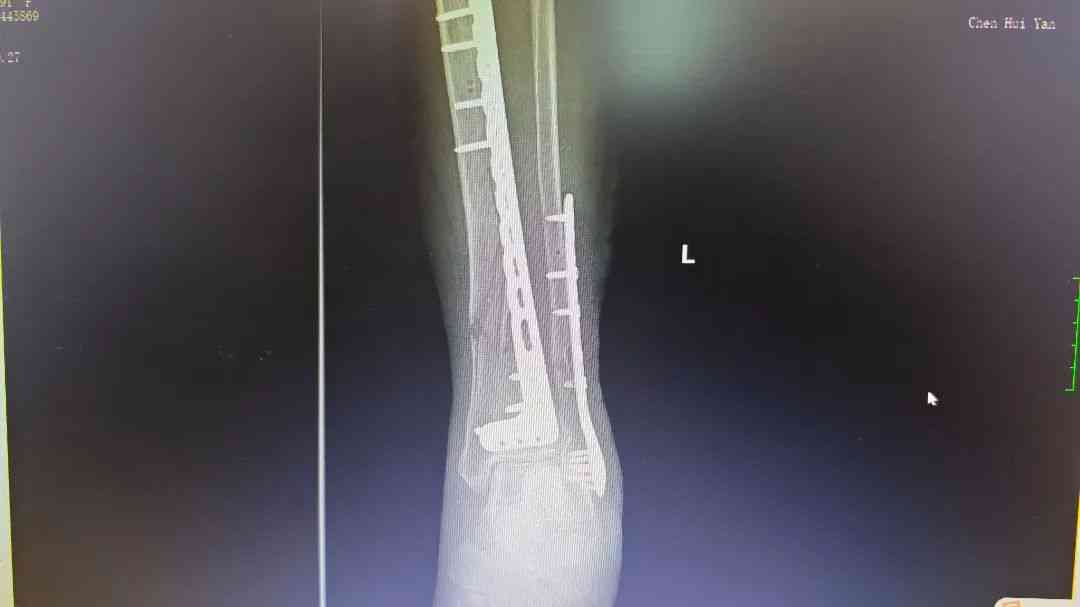

微信图片_20250512172734.jpg 微信图片_20250512172737.jpg

术后腿部影像

胸外科专家会诊后确认,患者肋骨骨折无明显位移,决定采用胸带固定配合卧床静养的保守治疗方案。针对更为复杂的小腿骨折,骨科团队在5月4日由张均锦主刀,曹桂青、陆仕邦医师协助下实施了精准复位手术。术中使用接骨板进行内固定后,X光显示骨折端对位良好,术后第三天患者已能进行简单的足部活动。